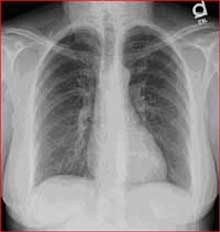

Normal Chest X-Ray